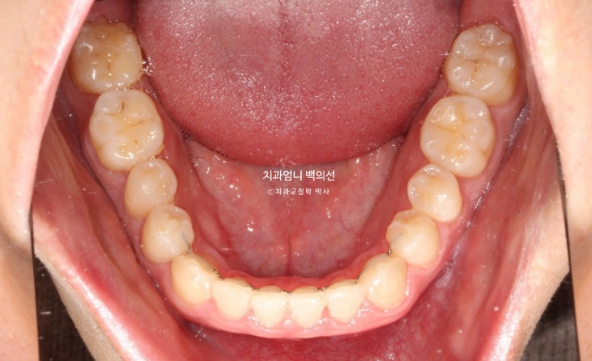

You can see a well-aligned midline and a good bite.

If the molar bite is not perfect, we do not finish treatment.

This is how it looks with the wire retainer in place.

In the front teeth area, once the open bite and reverse bite were corrected, a stable bite was created.